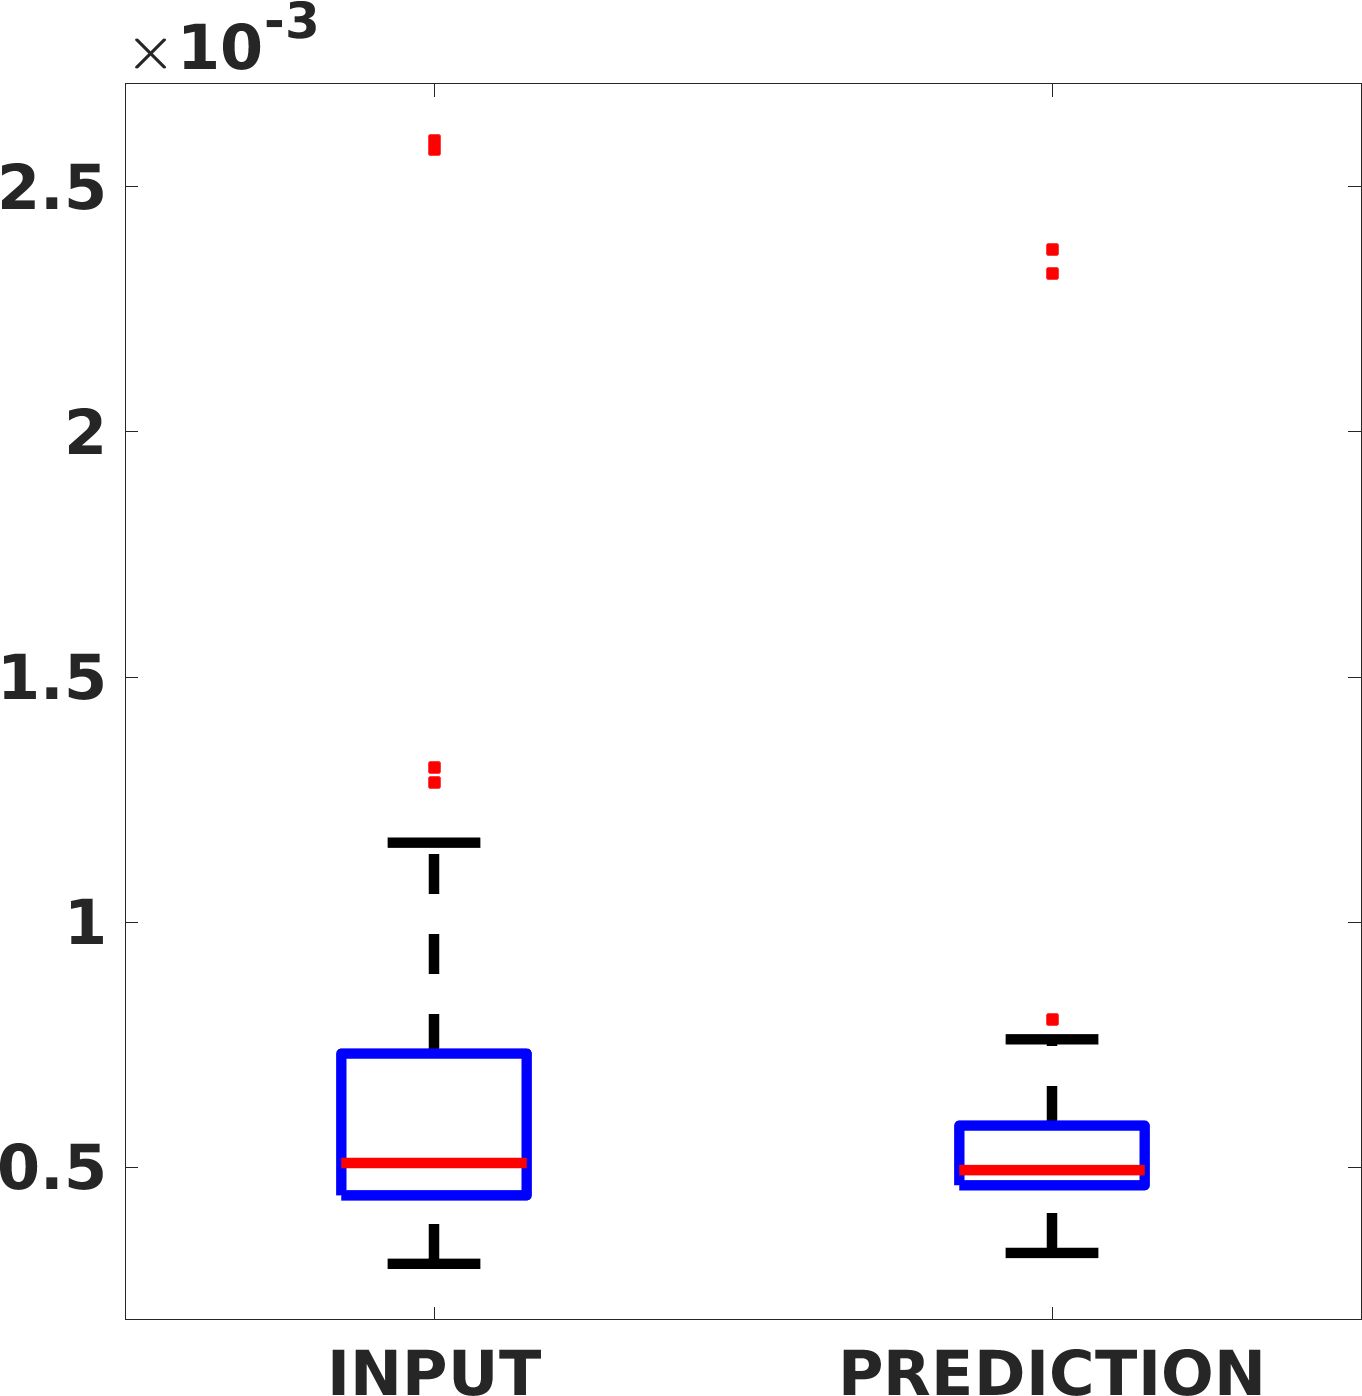

Fig. 8 shows the box plot of the SSIM (a-b-c, left) and MAE (a-b-c, right) quantitative metrics, as performed for PSNR metric. Also, these metrics show that our method improves the results of Cubic convolution both in terms of average value and variability. For example, the SSIM median value improves of on obstetric 4X images and the MAE median value improves of on cardiac 2X images.

Fig. 17 (left) shows the box plot of the quantitative metrics, comparing the target images with the prediction and the Cubic convolution, respectively. The PSNR metric is computed on a data set of 200 images, belonging to the same district, and with the same up-sampling factor. Analysing the obstetric anatomical district and concerning the corresponding raw images (Fig. 7 (a, left)), the denoising allows the network to significantly improve the results of the up-sampling and the prediction. In particular, comparing the target images with the predicted images, the median PSNR value of obstetric 2X denoised images is 51.8, compared to the median PSNR value of obstetric 2X raw images which is 36.9.

Fig. 17 (right) shows the histogram of the absolute value of the error with respect to the target, of the prediction and Cubic convolution respectively. This result shows that our framework increase of and (2X and 4X, respectively) the number of pixels where the prediction error is lower than 5, which is very similar to the target when visually analysing the images, and improved with respect to the learning framework applied to raw images. According to Fig. 18, our method improves the accuracy of Cubic convolution. For example, the SSIM increases of on cardiac 2X and the MAE increases of on abdominal 4X.